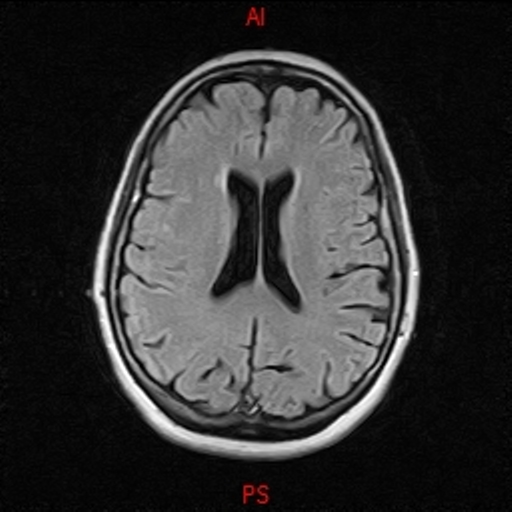

• RESONANCIA NORMAL CRANEAL T2 AXIAL

• RESONANCIA NORMAL CRANEAL T1 AXIAL